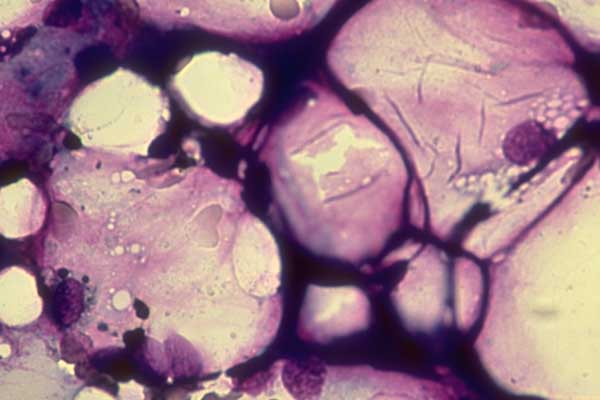

Il processo avviene in una parte di una cellula detta mitocondrio, un organulo del citoplasma addetto alla respirazione cellulare, spiega il prof. David James, direttore del programma di ricerca su diabete e obesita’ dell’Istituto. ‘Se si mangiano le giuste quantita’ di cibo, la maggior parte delle sostanze nutritive si trasforma in produzione di energia e tutto va bene. Ma se si mangia troppo e male, il mitocondrio si sovraccarica di nutrimento, che invece di convertirsi in energia si trasforma in ossidanti, i quali causano resistenza all’insulina’. Quando l’insulina perde la capacita’ di operare sui muscoli e sulle cellule di grasso, il pancreas comincia a secernere insulina in eccesso, fino a quando il pancreas si debilita e insorge il diabete. L’ipotesi e’ che l’organismo produca ossidanti nel mitocondrio come meccanismo naturale di difesa. ‘Il meccanismo di resistenza all’insulina puo’ essere una maniera in cui la cellula cerca di bloccare un sovraccarico di nutrimento’, scrive. Il prossimo passo sara’ di sviluppare farmaci antiossidanti specifici.